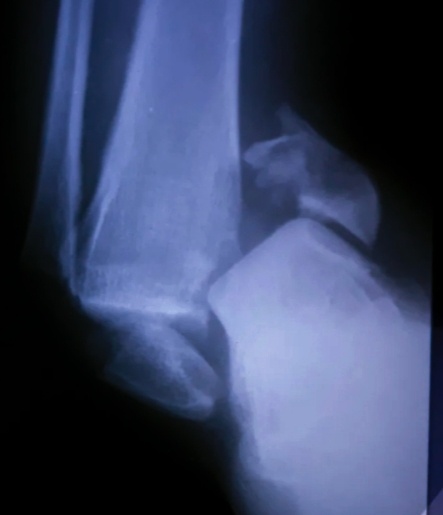

Завезла санитарка приемника Юля на каталке пациента, 25 лет, назначен снимок голени и легких.Нога (стопа ) неестественно вывернута, наверное еще и вывих.

Потом голень сняла. Да, переломы приличные, хотя могло быть и хуже.

-2

Самый нижний отдел костей пострадал.

Ногу я снимала, не трогая ее, использовала подручные средства, чтобы не доставить еще большей боли пациенту.